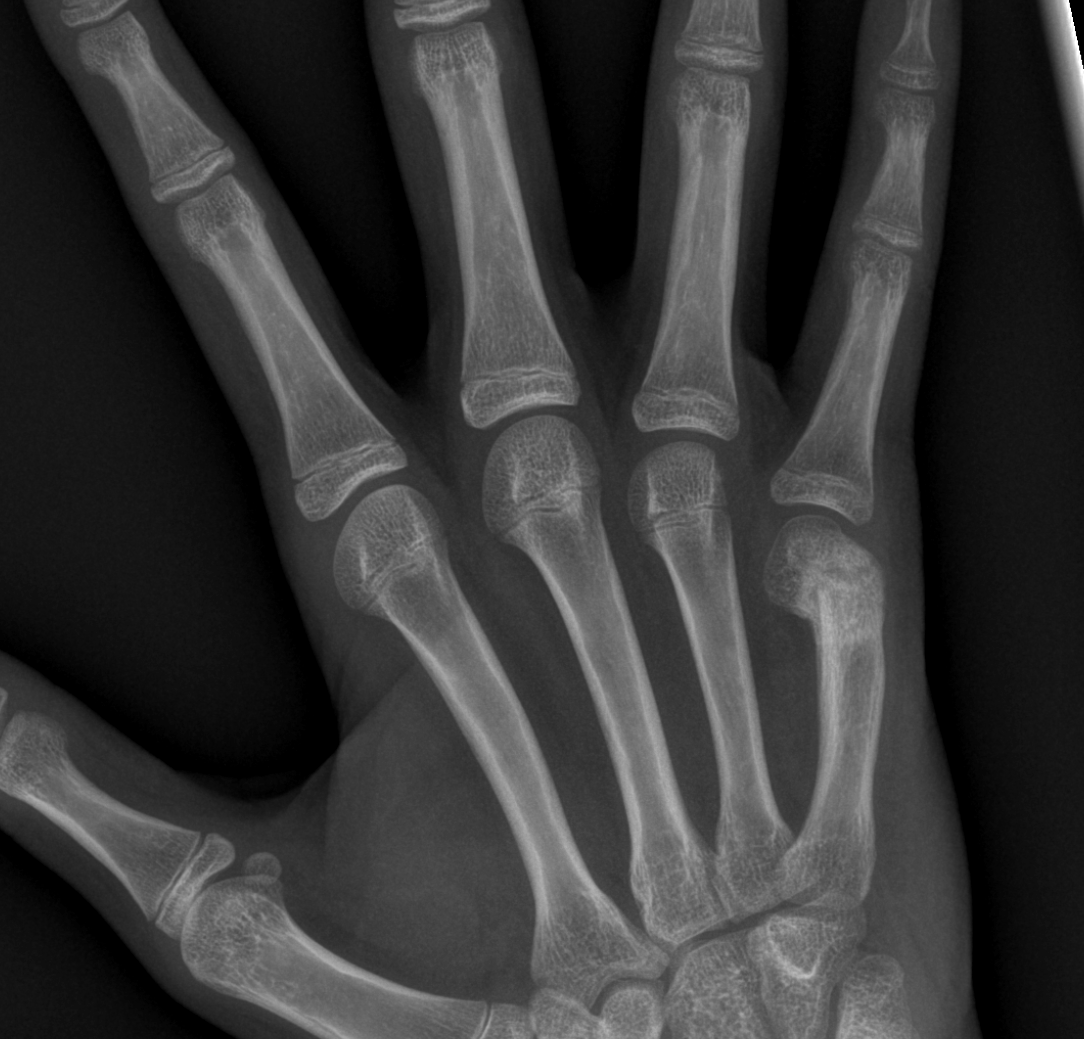

Info Images Findings Impression Reco/Acuity Case Images View Images / Launch Visage Case Notes History 2-month-old presents with decreased right arm movement, increased fussiness, and increased sleepiness for 2 days. Suspected non-accidental trauma. Exam Skeletal survey Prior Study none Dicom View Reference Material

Section 1 Submit Findings CB1550 Findings Skeletal Survey - Technique Check Skull AP/Lat Yes No Cervical and Thoracolumbar spine Yes No Chest X-Ray Yes No Ribs – Left/Right Oblique Yes No Abdominal X-Ray Yes No Pelvis with both hips Yes No Bilateral Humerus, Forearm, Hand Yes No Bilateral Femur, Tibia/fibula, feet Yes No Any additional lateral views of the extremities Yes No The exam is over or under penetrated. Yes No The exam may or may not be limited by overlying structures or soft tissues, body habitus, patient positioning, support devices, or motion. Yes No The area of concern is indicated by the patient, technologist, or care provider. Yes No The area of concern is included on the exam. Yes No Soft Tissues There is soft tissue swelling, indistinctness of fat/muscle planes, gas, or laceration in the area of clinical concern. Yes No There is an effusion, fat pad displacement, or fat fluid level. Yes No There is a radiodense or lucent foreign body. Yes No There are other densities, calcifications, post-surgical changes, or support devices in the soft tissues. Yes No Any support lines/tubes. Yes No Bone There is a break or interruption of the continuity of the cortical or cancellous bone. Yes No There is overriding of the trabeculae with apparent sclerosis. Yes No There is displacement of a fracture fragment. Yes No There is bowing of the bone in addition to the fracture at the apex of the bowed bone concerning for the greenstick. Yes No There is a spiral fracture of the leg concerning for toddler’s fracture. Yes No There is abnormal angulation or bulging of the cortical surface relative to the normal cortex which could be from a buckle or torus fracture. Yes No There is a displaced fragment which may be from avulsion by a tendon, ligament, or joint capsule or from a comminuted or other fracture. Yes No The stress trabeculae or other trabeculae of the cancellous bone are interrupted or otherwise abnormal. Yes No There is subperiosteal or endosteal reaction which could indicate a healing or subacute fracture or other abnormality. Yes No There is hard/soft callus formation. Yes No There is remodeling of the bone. Yes No There is a corner fracture or metaphyseal lesion that could be from nonaccidental trauma. Yes No There are multiple fractures of different ages. Yes No There are vertebral body/spinous process fractures. Yes No There are rib fractures. Location - posterior or lateral. Yes No There is scapular/sternal fracture. Yes No There are fractures of the digits. Yes No There are wormian bones. Yes No There are intrasutural bones. Yes No There is metaphyseal abnormality (lucencies, increased density, erosion) which may be from something other than injury such as stress, metabolic disease (e.g. rickets with loss or distortion of the zone of the provisional calcification), neoplasm (e.g. leukemia), heavy metals, inflammation, or infection. Yes No There are metaphyseal spurs. Yes No There are bony deformities involving multiple bones. Yes No The bones are gracile. Yes No There are non-healing fractures. Yes No There is/are focal or multifocal lytic/lucent, blastic/sclerotic or mixed density lesion(s) or other abnormality. Yes No Overall bone density is increased or decreased with or without thinning or thickening of the cortical or cancellous bone. Yes No Growth plates, ossification centers, apophyses The growth plate(s) is/are abnormal. Yes No There is widening of the physis from a fracture with or without displacement of the epiphysis (Salter-Harris I). Yes No There is a fracture through the physis which then extends into the metaphysis with or without angulation or displacement (S-H II). Yes No There is a fracture through the physis which then extends into the epiphysis and is intra-articular, with or without angulation or displacement (S-H III). Yes No There is a fracture through the metaphysis, physis, and epiphysis which extends into the joint space with or without angulation or displacement (S-H IV). Yes No There is narrowing of the physis from a compression fracture (S-H V). Yes No The apophysis, epicondyle, secondary ossification center, or accessory ossicle is displaced or otherwise abnormal. Yes No The ossification centers are underdeveloped. Yes No Joints and alignment There is an effusion, fat pad displacement, or fat fluid level. Yes No The epiphysis or subchondral bone is fractured, interrupted, flattened, compressed, impacted, displaced, or otherwise abnormal. Yes No There is an intra-articular loose body or chondrocalcinosis. Yes No The joint is widened, narrowed, dislocated, malaligned, or incongruent. Yes No There is pseudoarthrosis. Yes No Other findings There are developmental changes or other anatomic variants or other existing conditions that may or may not be contributing to symptoms which can or should be further evaluated non-emergently or are otherwise incidental. Yes No The remainder of the exam is abnormal for age. Yes No The lungs show focal airspace opacity. Yes No There is pneumothorax. Yes No There is organomegaly. Yes No There is intra-abdominal calcification. Yes No There is displacement of the bowel loops. Yes No There is free intraperitoneal air. Yes No The bowel loops are dilated/obstructed. Yes No There is paraspinal soft tissue abnormality. Yes No